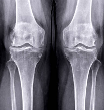

✅ 앞무릎 관절염이란? (슬개대퇴 통증 증후군)

앞무릎 관절염은 일반적으로

슬개골(무릎 앞의 동그란 뼈)과 대퇴골(허벅지 뼈)의 마찰로 인해 연골이 손상되면서

무릎 앞쪽에 국한된 통증이 반복되는 질환입니다.

- X-ray, MRI 상 슬개대퇴 간격이 좁아져 있거나 연골 마모가 보이는 경우